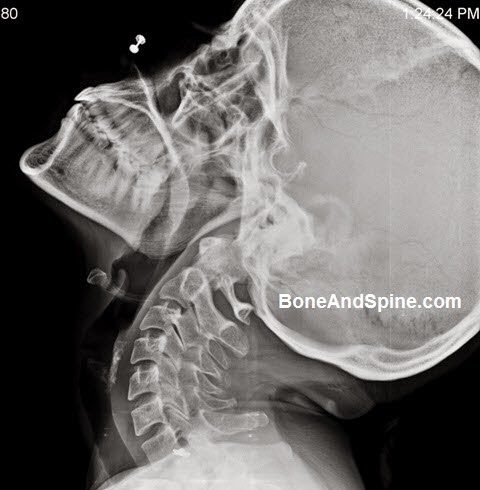

| c1 (top) – c7 (bottom)* |

There are less protrusions and more gaps toward the top, and more bony points and stackable processes, limiting movement toward the bottom.